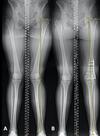

A 40-year-old man who is a manual laborer has had 3 years of worsening medial-sided left knee pain that has inhibited his ability to work. He reports undergoing a left subtotal medial menisectomy 10 years ago. He has been treated with nonsteroidal anti-inflammatory drugs and 2 different corticosteroids, with the most recent injection given 1 month ago. Each injection provided him with a few weeks of pain control. His medical history is unremarkable and he has smoked 20 cigarettes per day for the last 15 years. His body mass index (BMI) is 22. On examination, he has varus alignment of the involved leg and medial joint line tenderness and no lateral or patellofemoral pain. His knee range of motion is 3° shy of full extension to 130° of flexion. He has negative Lachman and posterior drawer test results. He demonstrates no lateral thrust with ambulation. What imaging study is most appropriate to determine treatment options for this patient? Based on his exam, what should be the next step in management after imaging?

This patient has a classic presentation of postmeniscectomy medial compartment arthritis. The appropriate diagnostic study is weight-bearing radiographs to confirm the diagnosis. An MRI scan will reveal medial compartment arthritis but will not provide information about alignment. A CT scan would be appropriate to detect an occult fracture; however, this condition is not suspected in this clinical scenario. Ultrasonography can provide information about fluid collection around the knee or a deep vein thrombosis; however, these conditions also are not suspected in this clinical scenario. Because the patient has a correctable deformity (gaps 3 mm with valgus stress), and his symptoms are localized to the involved compartment, a trial of a medial unloader brace is appropriate both diagnostically and therapeutically. If unloading the medial compartment resolves the patient's symptoms, he would be an excellent candidate for an osteotomy. An MRI scan may be obtained to evaluate ligamentous integrity or to evaluate degenerative involvement of the lateral and patellofemoral compartment for presurgical planning of an osteotomy; however, the integrity of the medial meniscus has no clinical importance in a patient with severe medial compartment arthritis. A repeat corticosteroid injection is not indicated within 1 month of his last injection, and referral to pain management is not appropriate with other options available to help this patient. A VPHTO is the appropriate intervention considering the patient's young age, high-functional occupation, examination, radiographic findings, and response to medial unloader bracing. A revision knee arthroscopy would be appropriate for a recurrent medial meniscus tear, but not appropriate in a patient with severe medial compartment arthritis. The patient's young age and high functional requirements are contraindications to TKA. The presence of severe arthritis is a contraindication to medial meniscus transplant. The patient is a candidate for a VPHTO. The technical options include a medial opening-wedge or a lateral closing-wedge osteotomy. Both techniques have advantages and disadvantages; however, a medial opening-wedge osteotomy is contraindicated in a smoker because of concern for nonunion. As a result, current smoking history is the only factor listed that would influence the technique used. The history of prior arthroscopy has no relevance in the decision about which type of osteotomy is appropriate. Normal BMI is between 18.5 and 24.9, so this patient's BMI is considered normal and would not affect the surgical technique (if this patient were obese, a lateral closing-wedge osteotomy would be considered, but this is controversial). His age of 40 years is an indication for HTO but does not influence technique.